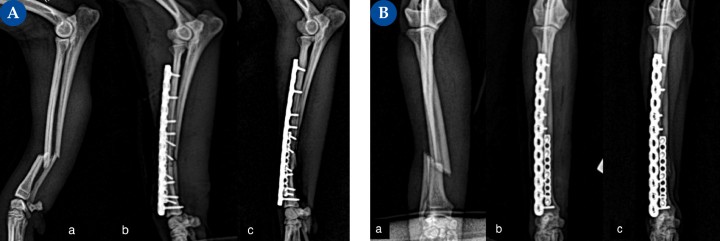

(A) Proyección mediolateral, (B) Proyección craneocaudal. Fractura diafisaria distal de cúbito y radio, oblicua corta en un lebrel italiano de 2,8 kg.(a) Fractura diafisaria distal de cúbito y radio, oblicua corta, con leve pérdida de stock óseo (fractura abierta, grado I).&nbsp;(b) En este caso, se opta por una estabilización con una placa principal en la cara craneolateral del radio mediante un implante bloqueado de titanio multiorificio poliaxial con tres tornillos bloqueados de 1,5 mm en el fragmento distal y cuatro en el fragmento proximal. Debido a la detección intraoperatoria de un defecto transcortical, se coloca una placa auxiliar en la cara medial del radio: placa bloqueada de titanio con dos tornillos de 1,2 mm bloqueados por fragmento. Gracias a esta configuración, podemos colocar cinco tornillos en el fragmento distal; utilizando una sola placa principal, solamente podríamos haber colocado tres.&nbsp;(c) Evolución de la consolidación ósea a las 6 semanas postoperatorias.

(A) Proyección mediolateral, (B) Proyección craneocaudal. Fractura diafisaria distal de cúbito y radio, oblicua corta en un lebrel italiano de 2,8 kg.(a) Fractura diafisaria distal de cúbito y radio, oblicua corta, con leve pérdida de stock óseo (fractura abierta, grado I). (b) En este caso, se opta por una estabilización con una placa principal en la cara craneolateral del radio mediante un implante bloqueado de titanio multiorificio poliaxial con tres tornillos bloqueados de 1,5 mm en el fragmento distal y cuatro en el fragmento proximal. Debido a la detección intraoperatoria de un defecto transcortical, se coloca una placa auxiliar en la cara medial del radio: placa bloqueada de titanio con dos tornillos de 1,2 mm bloqueados por fragmento. Gracias a esta configuración, podemos colocar cinco tornillos en el fragmento distal; utilizando una sola placa principal, solamente podríamos haber colocado tres. (c) Evolución de la consolidación ósea a las 6 semanas postoperatorias.